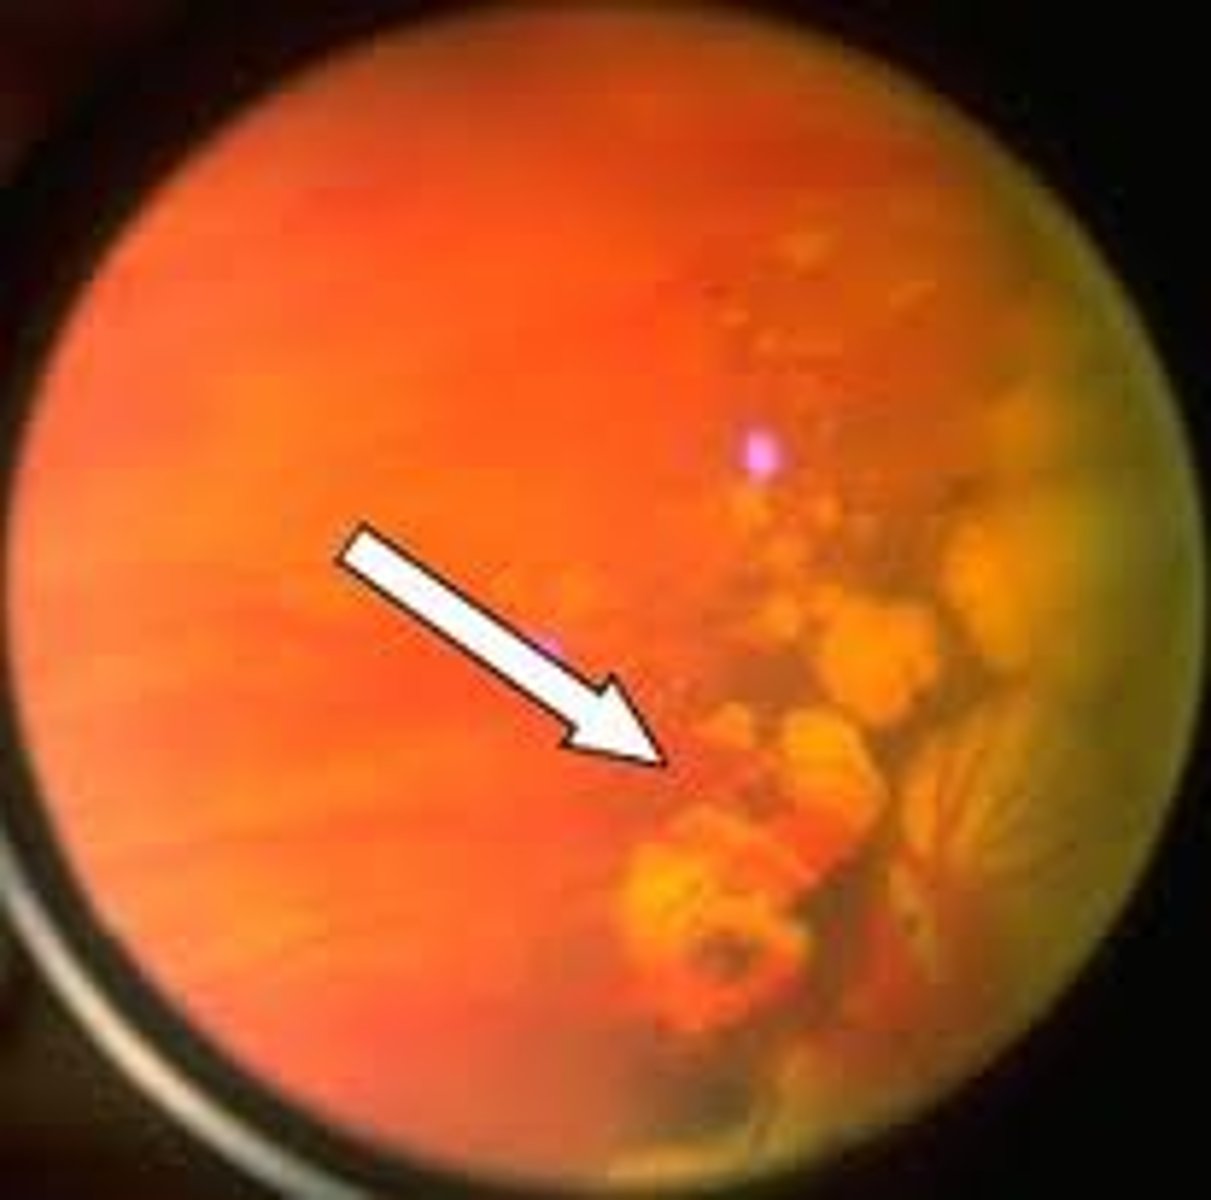

Equatorial drusen aetiology

Peripheral drusen

•Deposits of material on Bruch's membrane

•Found in over 70% of patients over 50 years of age

•Histologically similar to macula drusen

•Benign (as long as not approaching macula) and not associated with

any other conditions